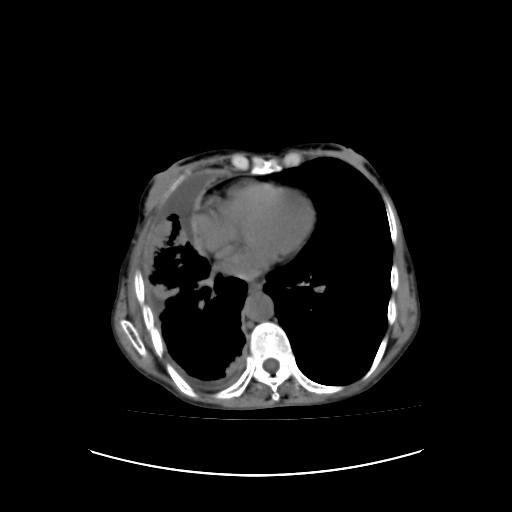

符合:恶性胸水的表现。多考虑恶性胸膜间皮瘤。

右侧胸廓塌陷,右侧胸膜广泛增厚并见多发胸膜结节,右侧少量胸腔积液并包裹。

可见多发肺内病灶,且胸膜病灶较多有圆球状而非丘状,多考虑胸膜转移瘤伴胸腔积液,右侧胸廓缩小固定,且部分病灶呈丘状,尚不除外恶性胸膜间皮瘤伴肺内转移